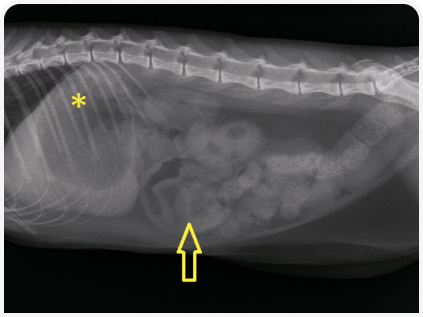

Пальпация брюшной полости без признаков отклонений не позволяет полностью исключить заболевания; даже при легкой форме заболевания проводят рентгенографию органов брюшной полости и в случае необходимости — хирургическое лечение. Если при рентгенографии не выявляют инородное тело (например, оно нерентгеноконтрастное), нужно оценить его непрямые симптомы, такие как центральное «скопление» петель кишечника (Рисунок 1) или аномальные пузырьки кишечного газа в форме полумесяца или слезы (5). Наличие так называемого симптома гравийных камешков указывает на хроническую кишечную непроходимость (Рисунок 2).

Инородные тела в кишечнике, помимо линейных, обычно вызывают его полную непроходимость с расширением краниально расположенных петель тонкой кишки (5). Аналогичным образом, в некоторых случаях хронических заболеваний ЖКТ (особенно у молодых кошек) может наблюдаться хроническая/динамическая инвагинация кишечника без явного расширения кишечных петель. Очень важно получить две, а лучше три рентгенограммы органов брюшной полости (лево- и правосторонние боковые и в ортогональной проекции), поскольку важнейшие нарушения могут выявляться только на одном снимке (Рисунок 3).